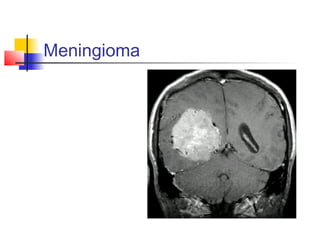

5. MENINGIOMAS

 In the atrium, and may be very large before

diagnosis.

 Presented with personality changes,

hydrocephalus, or neurological deficits.

 CT: isodense, often with calcification, and

take diffuse bright enhancement.

MRI: isointense inT1, hyperintense in

T2, with bright enhancement.

 Best treatment is surgical removal.

Meningioma

Masses of thelateral cerebral ventricle 5. MENINGIOMAS  In the atrium, and may be very large before diagnosis.  Presented with personality changes, hydrocephalus, or neurological deficits.  CT: isodense, often with calcification, and take diffuse bright enhancement. MRI: isointense inT1, hyperintense in T2, with bright enhancement.  Best treatment is surgical removal.

• 46.